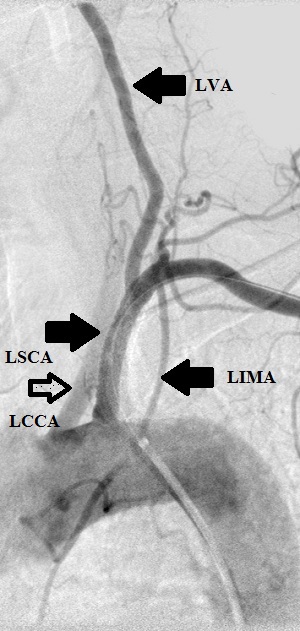

The 4 images you see above were recorded by me during primary stenting of irregular atherosclerotic stenosis of the left subclavian artery in a 54-year-old hispanic female who was referred to my interventional radiology clinic for management of the stenosis. She had presented to her primary care physician with symptoms of hindbrain ischemia upon using her left upper limb and earlier workup confirmed left subclavian arterial stenosis. The 2 top images illustrate the character and severity of her disease, the first image in the bottom row shows the process of balloon-expandable stenting of the disease, while the 2nd image in the bottom row reveals complete elimination of the stenosis and reappearance of the left vertebral and internal mammary arteires, which were invisible on the pre-intervention angiograms reflecting the severity of the stenosis.